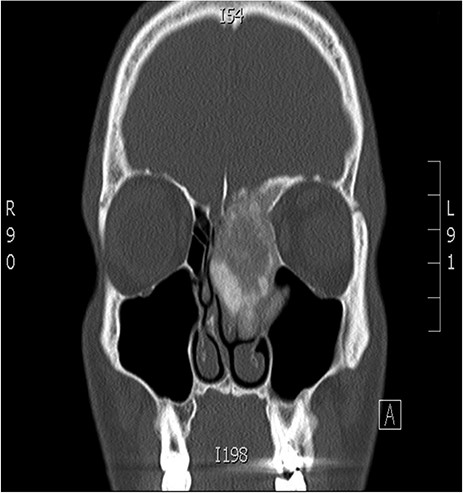

A 34-years-old man presented with left-sided facial pain, headache and nasal obstruction for a long duration, with no history of bleeding per nose, nor blurring of vision. Upon examination, there was a large left nasal cavity bony outgrowth pushing the middle turbinate and pushing the nasal septum to the right side (Fig. 1). CT scan of the paranasal sinuses showed a large mass centered in the left anterior ethmoid sinus, the mass measures 3.7 × 2.9 cm (trans-axial) (Fig. 2) and 3.7 × 5.2 cm (coronal) (Fig. 3), it has a heterogeneous density with calcified and soft-tissue component. The calcified component is in the periphery with central soft tissue density. The mass resulted in remodeling of adjacent bones with nasal septal deviation to the right, it extended superiorly to involve the frontal sinuses as well as invading the left cribriform plate and intracranial extension (Fig. 4), it extended inferiorly displacing the medial wall of the left maxillary antrum. The medial aspect of the mass caused remodeling of the medial wall of the left orbital cavity with bulging and displacement of the medial rectus muscle. The mass resulted in obstruction of the left frontal sinus.

Coronal CT image of the sinuses showing a large mass obstructing the frontal sinus.

Coronal CT image of the sinuses showing a mass encroaching the orbit and skull base.